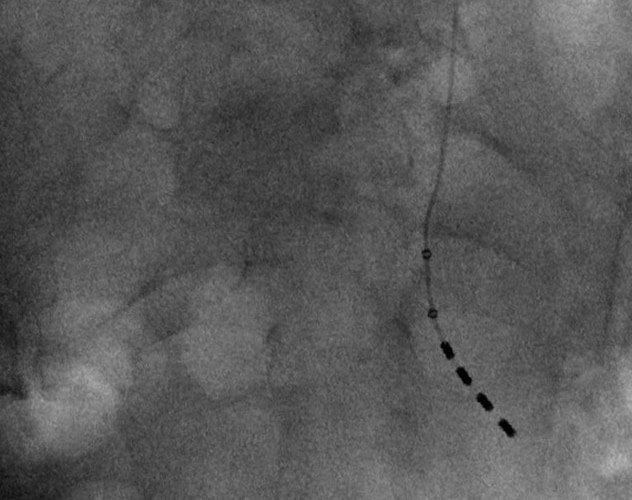

Further, 1.8% underwent pelvic floor physical therapy, 26% were referred to a specialist, and ultimately 2% underwent third line therapy. Third line therapies include onabotulinumtoxinA injection, percutaneous tibial nerve stimulation or sacral neuromodulation.

Use of third line therapies increased significantly (from 1.1% to 2.2%) over the study time frame. Of those patients who were treated with a third line therapy, the proportion of sacral neuromodulation decreased consistently and onabotulinumtoxinA increased. In the final year of the study (2017), the breakdown of third line treatments showed that onabotulinumtoxinA represented 37.8% of cases, sacral neuromodulation represented 36% of cases and tibial nerve stimulation represented 31.5% of cases. Referral to a specialist in urology or obstetrics and gynecology was associated with a significantly increased rate of third line therapy use.